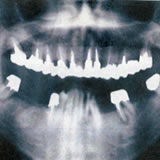

CTを導入

しています!

インプラントを埋める顎の骨には様々な重要な組織、血管や神経が集中しています。もしもこれらを傷つけた場合には、大出血を起こしたり、まひやしびれが起きることもあります。CT撮影をすると血管や神経が三次元的な状態で確認できますので事故を防ぐことが可能になり、インプラントでは必要不可欠な機器です。

インプラントを埋め込む顎の形や噛み合わせを診査するため、お口の中の型をとります。顎の骨の量や質を検査するためレントゲン撮影、またはCT撮影を行います。